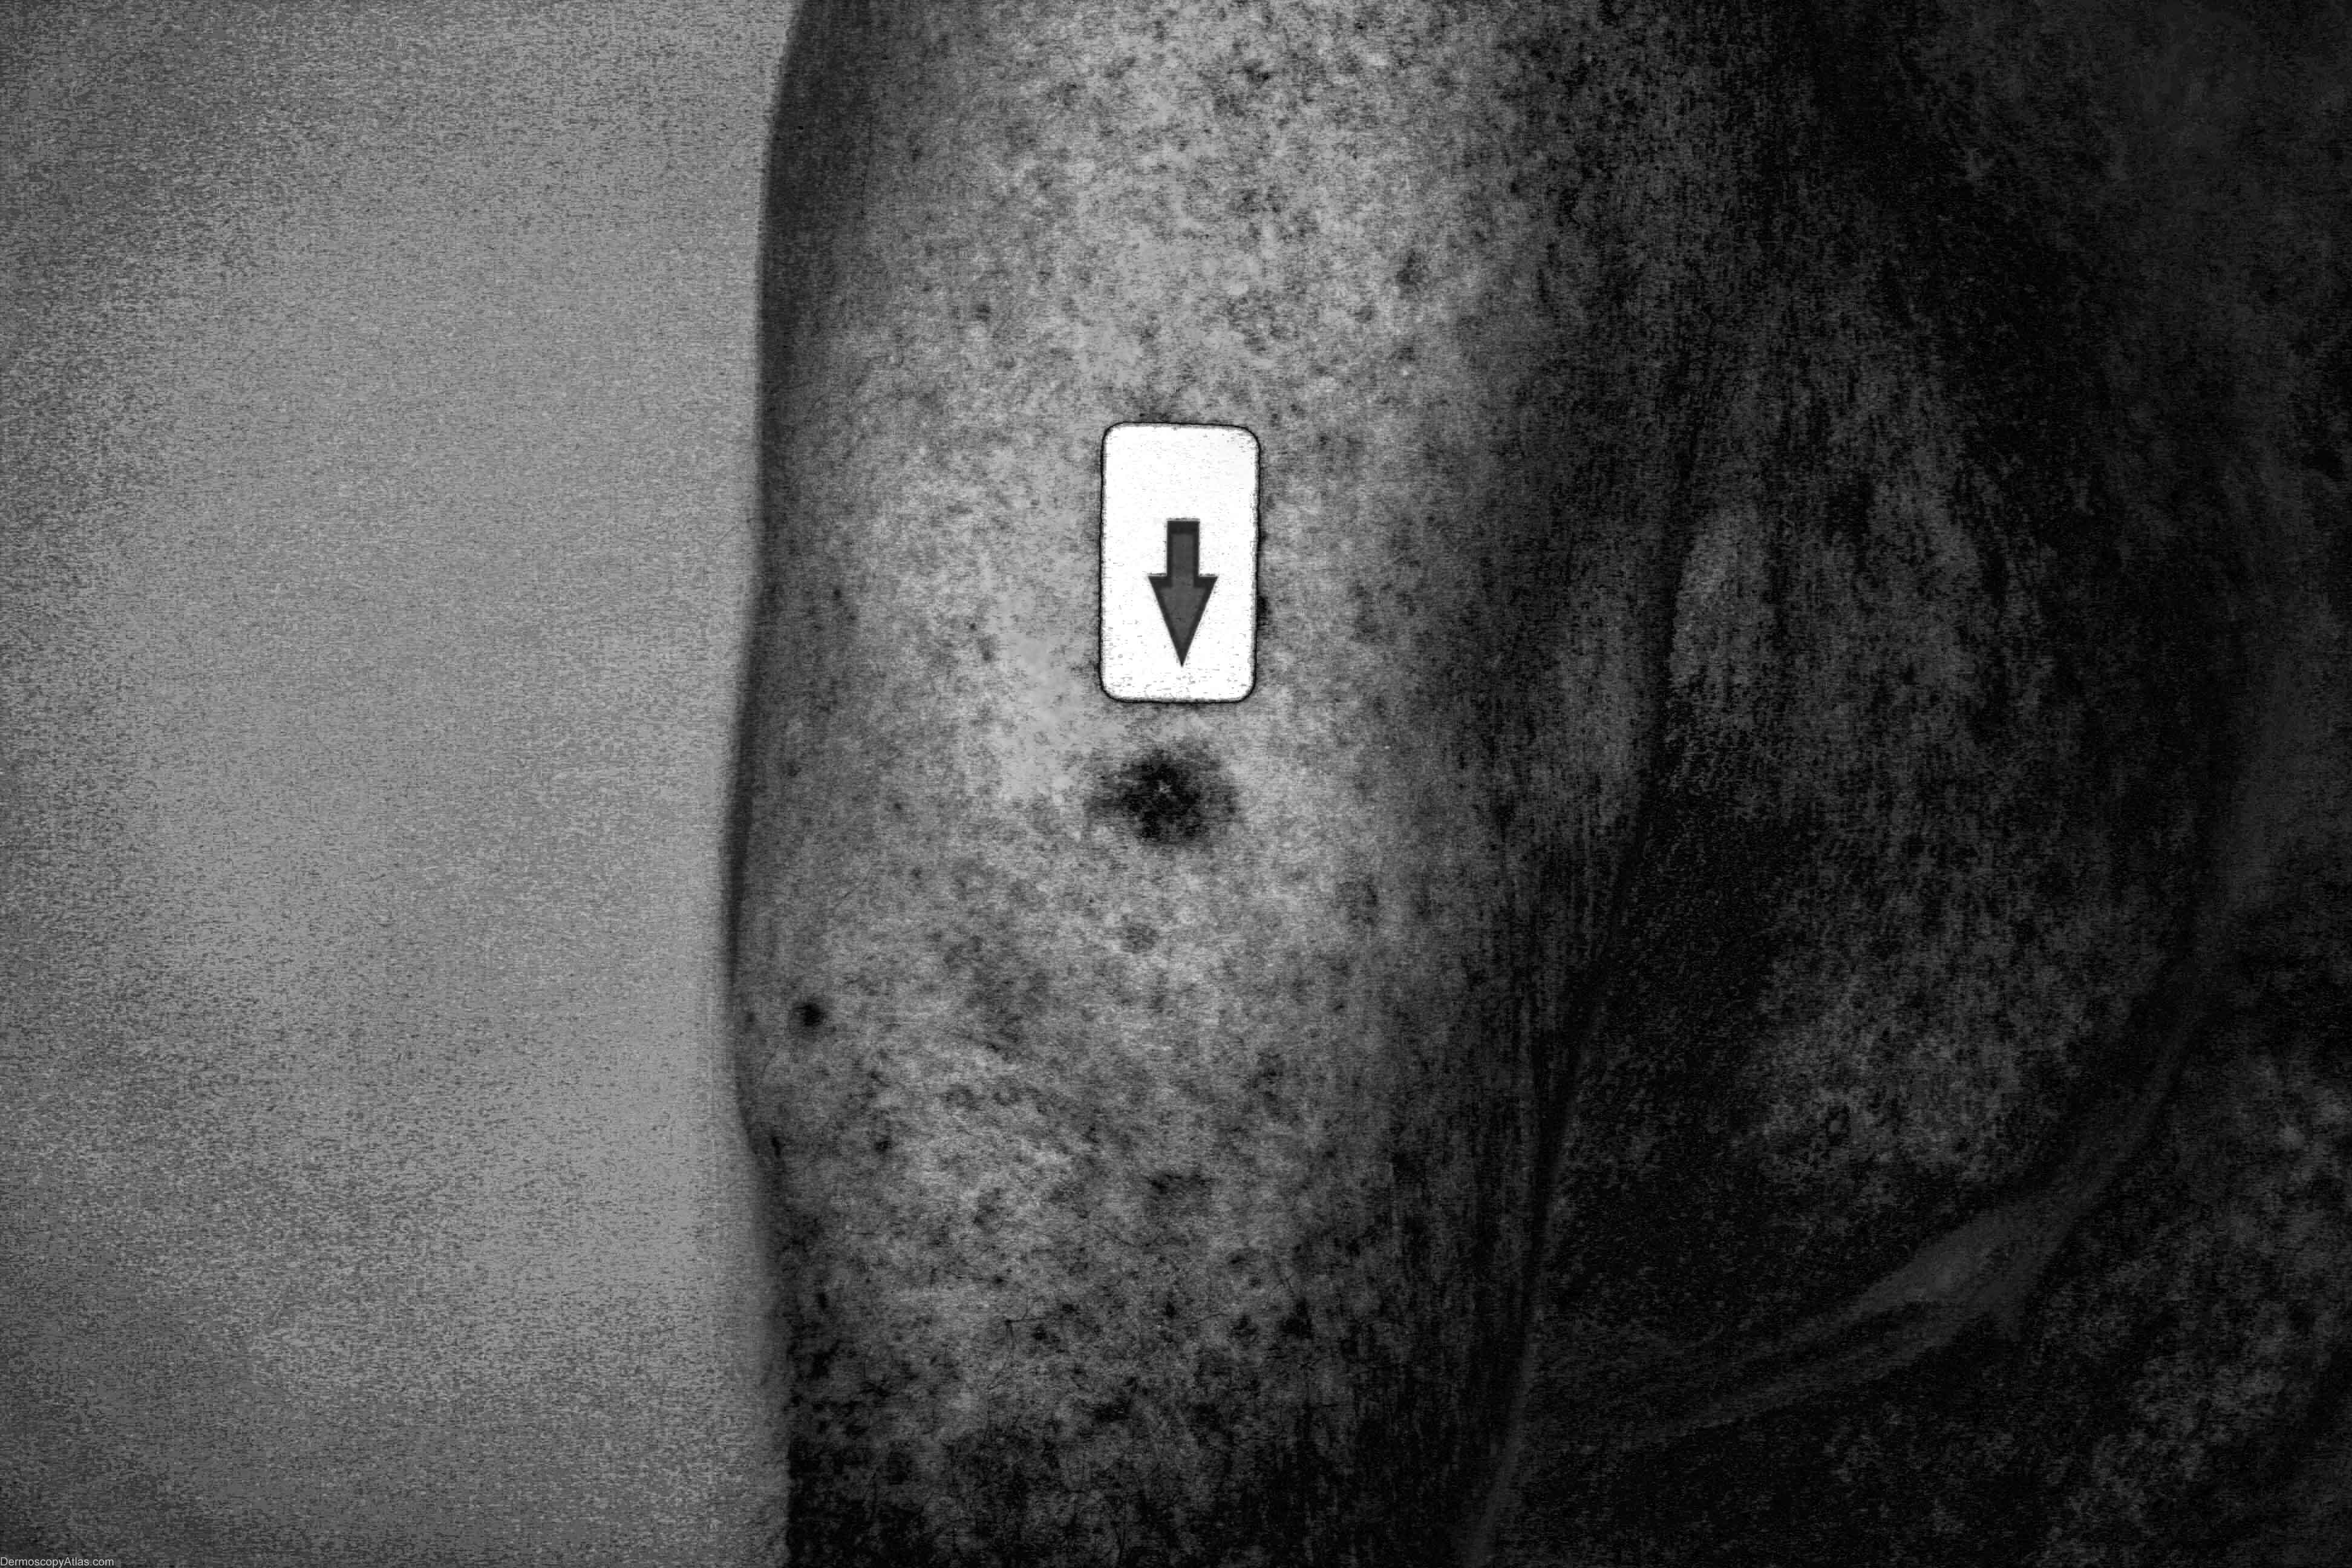

Site: Arm,upper

Diagnosis: Melanoma amelanotic

Sex: M

Age: 87

Type: Dermlite Non Polarised

Submitted By: Cliff Rosendahl

Description: Clinical image of a small nodule

History: This 87 year old veteran of World War 2 had a regular skin examination ( Past history of non-melanoma skin cancers) and this small papule could not be confidently diagnosed clinically. It was thought to be benign but NMSC needed exclusion. It came back after a 4mm punch biopsy removal of the visible lesion as a level 3 amelanotic melanoma (Breslow thickness 1.3mm) with complete regression of the epidermal component. A further 1.5 cm clearance was obtained and the report came back as superficial spreading amelanotic melanoma (small residual level 2 0.3 mm thick)cleared by only 5mm. In retrospect, especially with enhancement of the image by Dr. Lester Cowell, the large insitu amelanotic melanoma can be visualised.